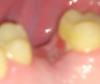

tester Опубликовано 11 мая, 2012 Автор Поделиться Опубликовано 11 мая, 2012 Фотоаппарат у меня мой временно забрали, пришлось мучиться сотовым снимать, ну вот что получилось выкладываю. Плюс сейчас зашёл сделал рентген, прошу оценить, чего там видно. У врача пока не был. Ссылка на комментарий

kriokov Опубликовано 11 мая, 2012 Поделиться Опубликовано 11 мая, 2012 (изменено) прошло 6 недель с момента удаления зуба, полного заживления лунки нет(судя по фото), это не нормально.На ренгенограммах больших изменений пазух нет, но это не значит , что дома надо сидеть, и ждать зарастет не зарастет. Диагноз только по снимку не выставишь.Со снимком к челюстно-лицевому хирургу. Он и будет определять- действительно ли определяется при зондировании ход из лунки удаленного зуба в пазуху, и если да, то что делать. И прицельный снимок в области удаленного 26 повторить можно. Смотреть все надо. Изменено 11 мая, 2012 пользователем kriokov 1 Ссылка на комментарий